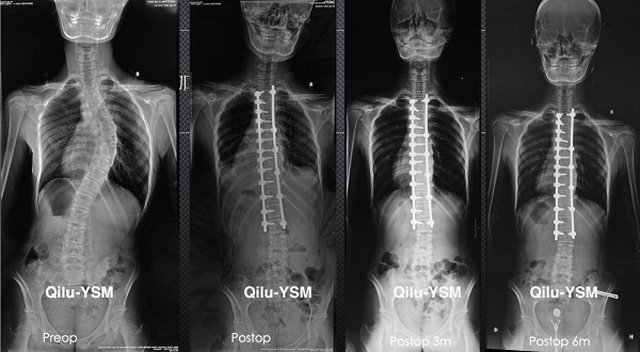

懸吊DR-全電動(dòng)型機(jī)架DR檢查主要用于胸部、四肢、關(guān)節(jié)、脊柱等,主要檢查肺部炎癥、腫瘤、結(jié)核病、四肢骨關(guān)節(jié)的骨折、四肢關(guān)節(jié)、脊柱外傷等。DR就是X光,是一種數(shù)碼影像,曝光時(shí)間很短,攝像量很小,影像質(zhì)量也很好,可以說是一種替代CR的方法。DR檢查有其局限性,需要做CT平掃等檢查,周圍淋巴結(jié)的轉(zhuǎn)移以確定病變的良惡性、范圍、大小、與鄰近組織的關(guān)系。